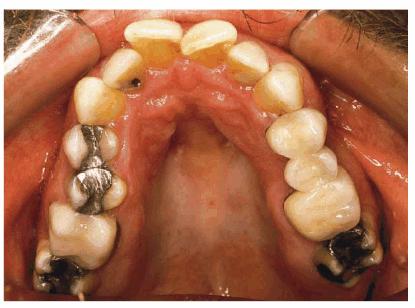

PROBLEM: This 38-year-old store owner presented with crowded and

discolored maxillary and mandibular teeth (Figures 24-7A, and 24-7B). Although orthodontic treatment was suggested as ideal

treatment, he elected a compromise that consisted of bonding the mandibular and

crowning the maxillary teeth.

Figure 24-7A: This 38-year-old man wanted to improve his crowded maxillary and mandibular teeth.

Figure 24-7B: This occlusal view shows why full orthodontic treatment was originally presented as the ideal treatment. The patient insisted on a "quick fix" solution.